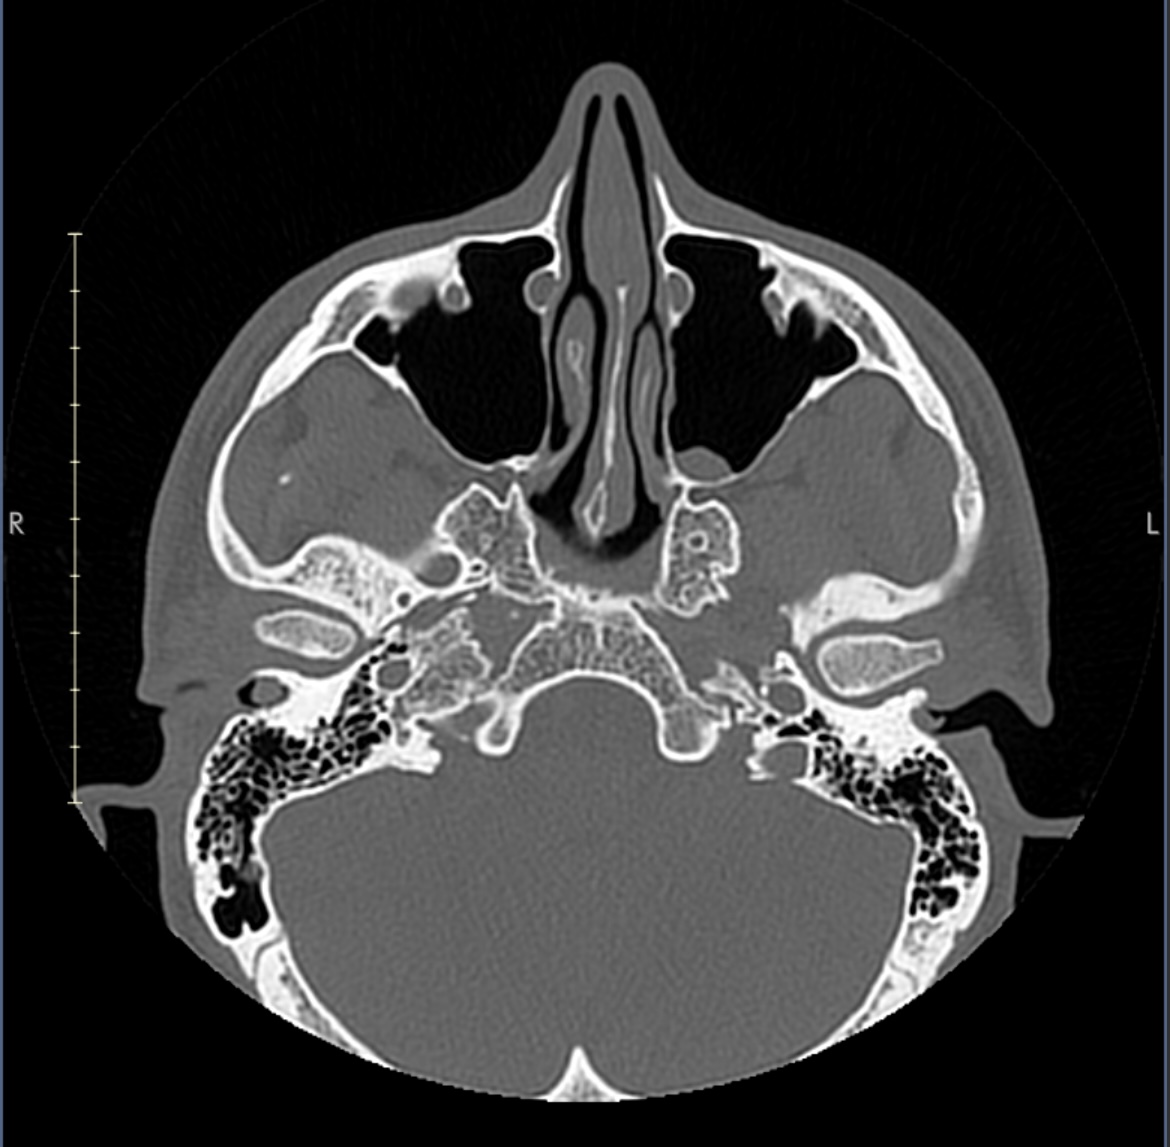

IMG 1347

Looking at this slice through my zygos I think my maxilla is flat.

But comparing my side profile to your chart it seems not flat.

I might just be on the borderline for flat. I’m certainly recessed but it appears to be mostly in the lower maxilla as my anterior nasal spine is set back from my upper nasal bone.. I don’t see how Lefort 2 alone would be good here, it would have to be segmental 2 and 1 combined.

It also raises a question about infraorbital implants because unless you already have an exemplary “3D” maxilla, they are going to flatten it out even more. I’m not sure my face can support them at all without Lefort 2.